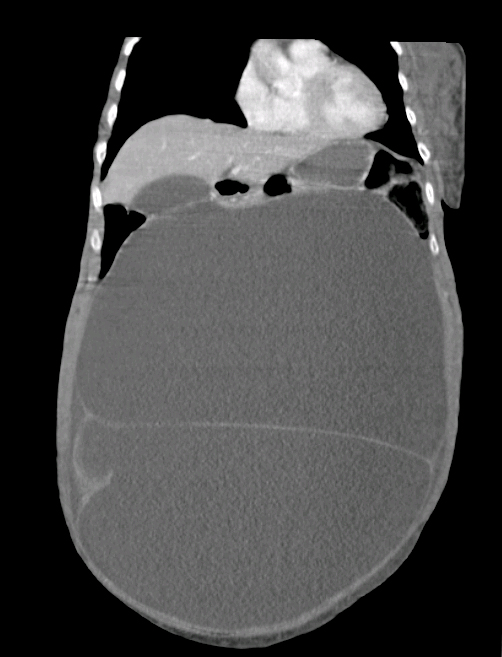

A frail 92-year-old woman presented with pelvic and femoral fragility fractures after a fall. She had synchronous gross abdominal distension which was diagnosed as ascites. Computed tomography was requested to exclude malignancy before performing paracentesis.

Formal imaging showed a large intraperitoneal structure. The 4-Hounsfield unit attenuation was consistent with simple fluid. However, identification of septations, together with rim enhancement, led to a revised diagnosis of a cystic mass. The lesion measured 24 cm × 28 cm × 33 cm and, at an estimated volume of 16 L, displaced most of the abdominal and pelvic viscera. Fortunately, this was recognised before paracentesis.